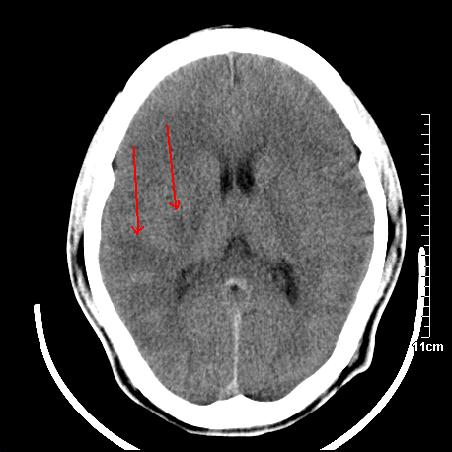

头晕.头痛间断意识恍惚1周 m/21y

4天上述症状加重伴左侧肢体发软,复查ct,

右侧放射冠可见点状低密度,可疑腔隙性梗塞

我当时诊断的是1.右侧底节区脑血栓形成

2.考虑少量蛛网膜下腔出血

3.右侧颞叶低密度区考虑脑血管畸形

因病人拒绝进一步检查,反复做工作后,病人做了腰穿,脑脊液化验显示有红细胞,呈现轻度红色